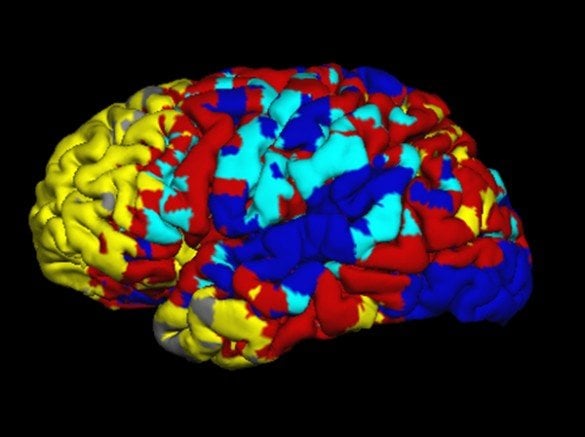

This is an fMRI of the brain during resting state.

Validating Maps of the Brain’s Resting State

A new study examines the relationship of fMRI maps of the brain's resting state with the brain's underlying neurological and anatomical structure.